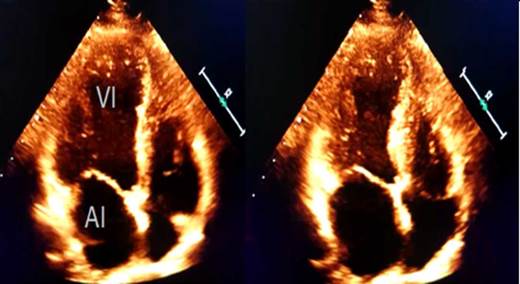

The echocardiogram performed on the same day of admission (Figure 2) also showed moderate left ventricular dysfunction with a LVEF of 38% associated with apical dyskinesia, involving akinesia of the mid-distal segments of the anterior wall, distal to the inferior wall, mid-distal to the lateral wall, and distal to the posterior interventricular septum, findings suggestive of apical ballooning. No right ventricular dysfunction was reported, and pulmonary artery systolic pressure was 60 mmHg, which was associated with mild tricuspid valve regurgitation.

Source: Own elaboration.

Figure 2 Echocardiogram in apical four-chamber view during the phases of diastole and systole. AI: left atrium; VI: left ventricle.